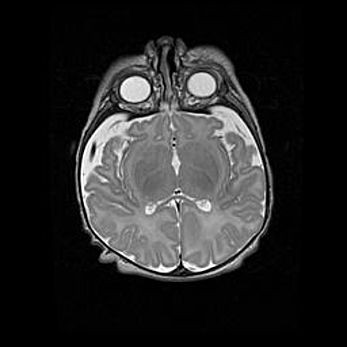

Наружная гидроцефалия с возможной атрофией височных областей.

Возраст: 28 дней

Вес: 3670 г

Пол: мужской

Окружность головы: 38 см

Срок гестации: 40 недель

Гидроцефалия головного мозга у новорожденных – это заболевание, которое характеризуется скоплением избыточного количества спинномозговой жидкости в желудочковой системе головного мозга в результате затруднения её перемещения от места выработки к месту поглощения в кровеносную систему или вследствие нарушения абсорбции. При открытой наружной форме гидроцефалии у новорожденных расширяются и переполняются субарахноидные пространства.

При нормотензивных  формах,  которые,  как  правило,  являются  следствием  перенесенных ишемических  повреждений  паренхимы  мозга,  возможно  сочетание микроцефалии  с нормотензивной гидроцефалией. В основе данных изменений лежит атрофия больших полушарий с преимущественной  локализацией  в  лобно-височных  областях.